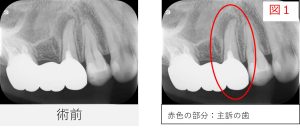

●レントゲン・CT画像所見

レントゲン写真およびCT画像にて、 右上5番の根尖部に黒い影(骨のない部分)が認められました。

また、根の後ろ側にも黒い影が確認され、 根の先だけでなく、側方にも病変が広がっている可能性が示唆されました。

この所見から、

- 側枝(主根管とは別の細い根管)の感染

- 歯根破折の可能性

といった点も考慮する必要があり、 原因を慎重に見極めながら治療を進める必要があると判断しました。